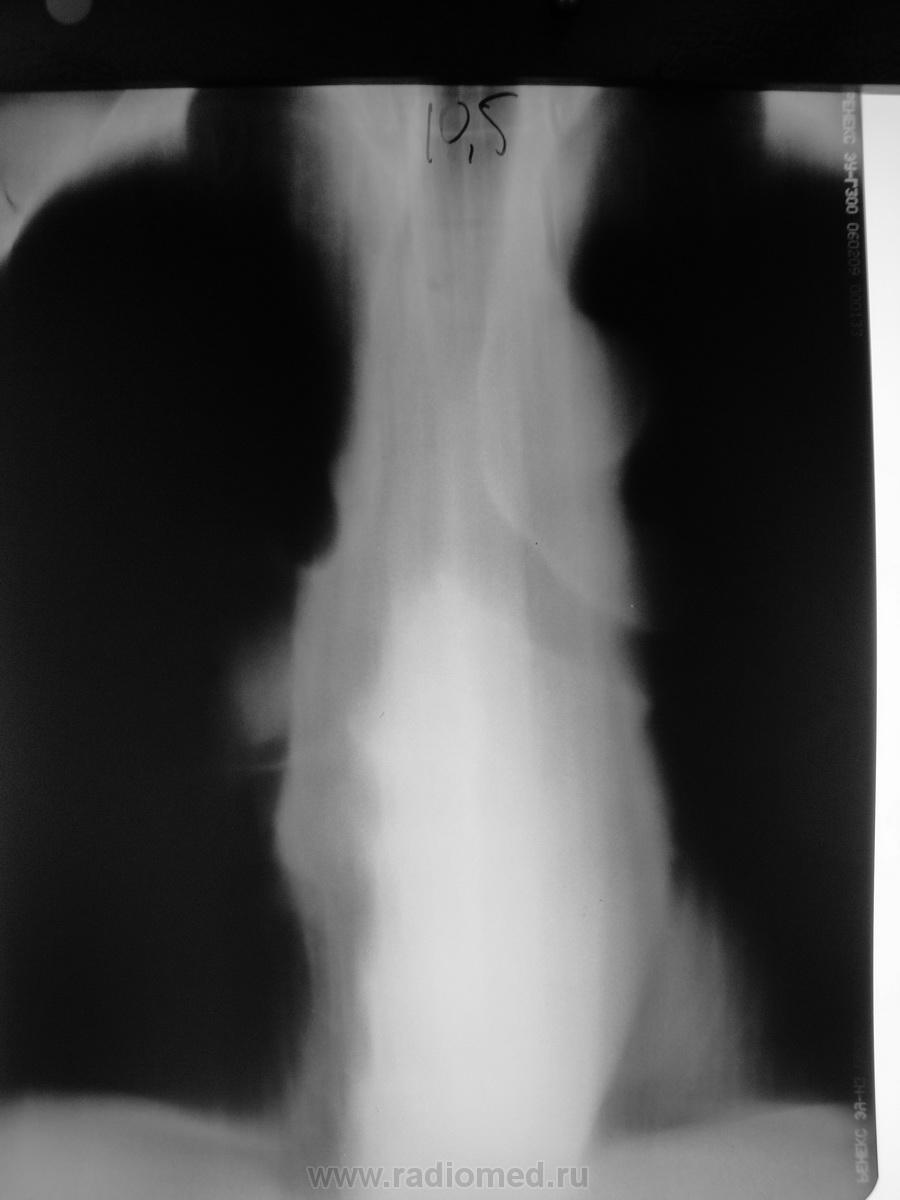

Снимки выполнены на разных аппаратах разными людьми с интервалом 3-4 дня..

На мой взгляд, такой корень обязательно должен быть оттомографирован при адекватных режимах.

Вот и "корешок" отобразился - явно нехороший.